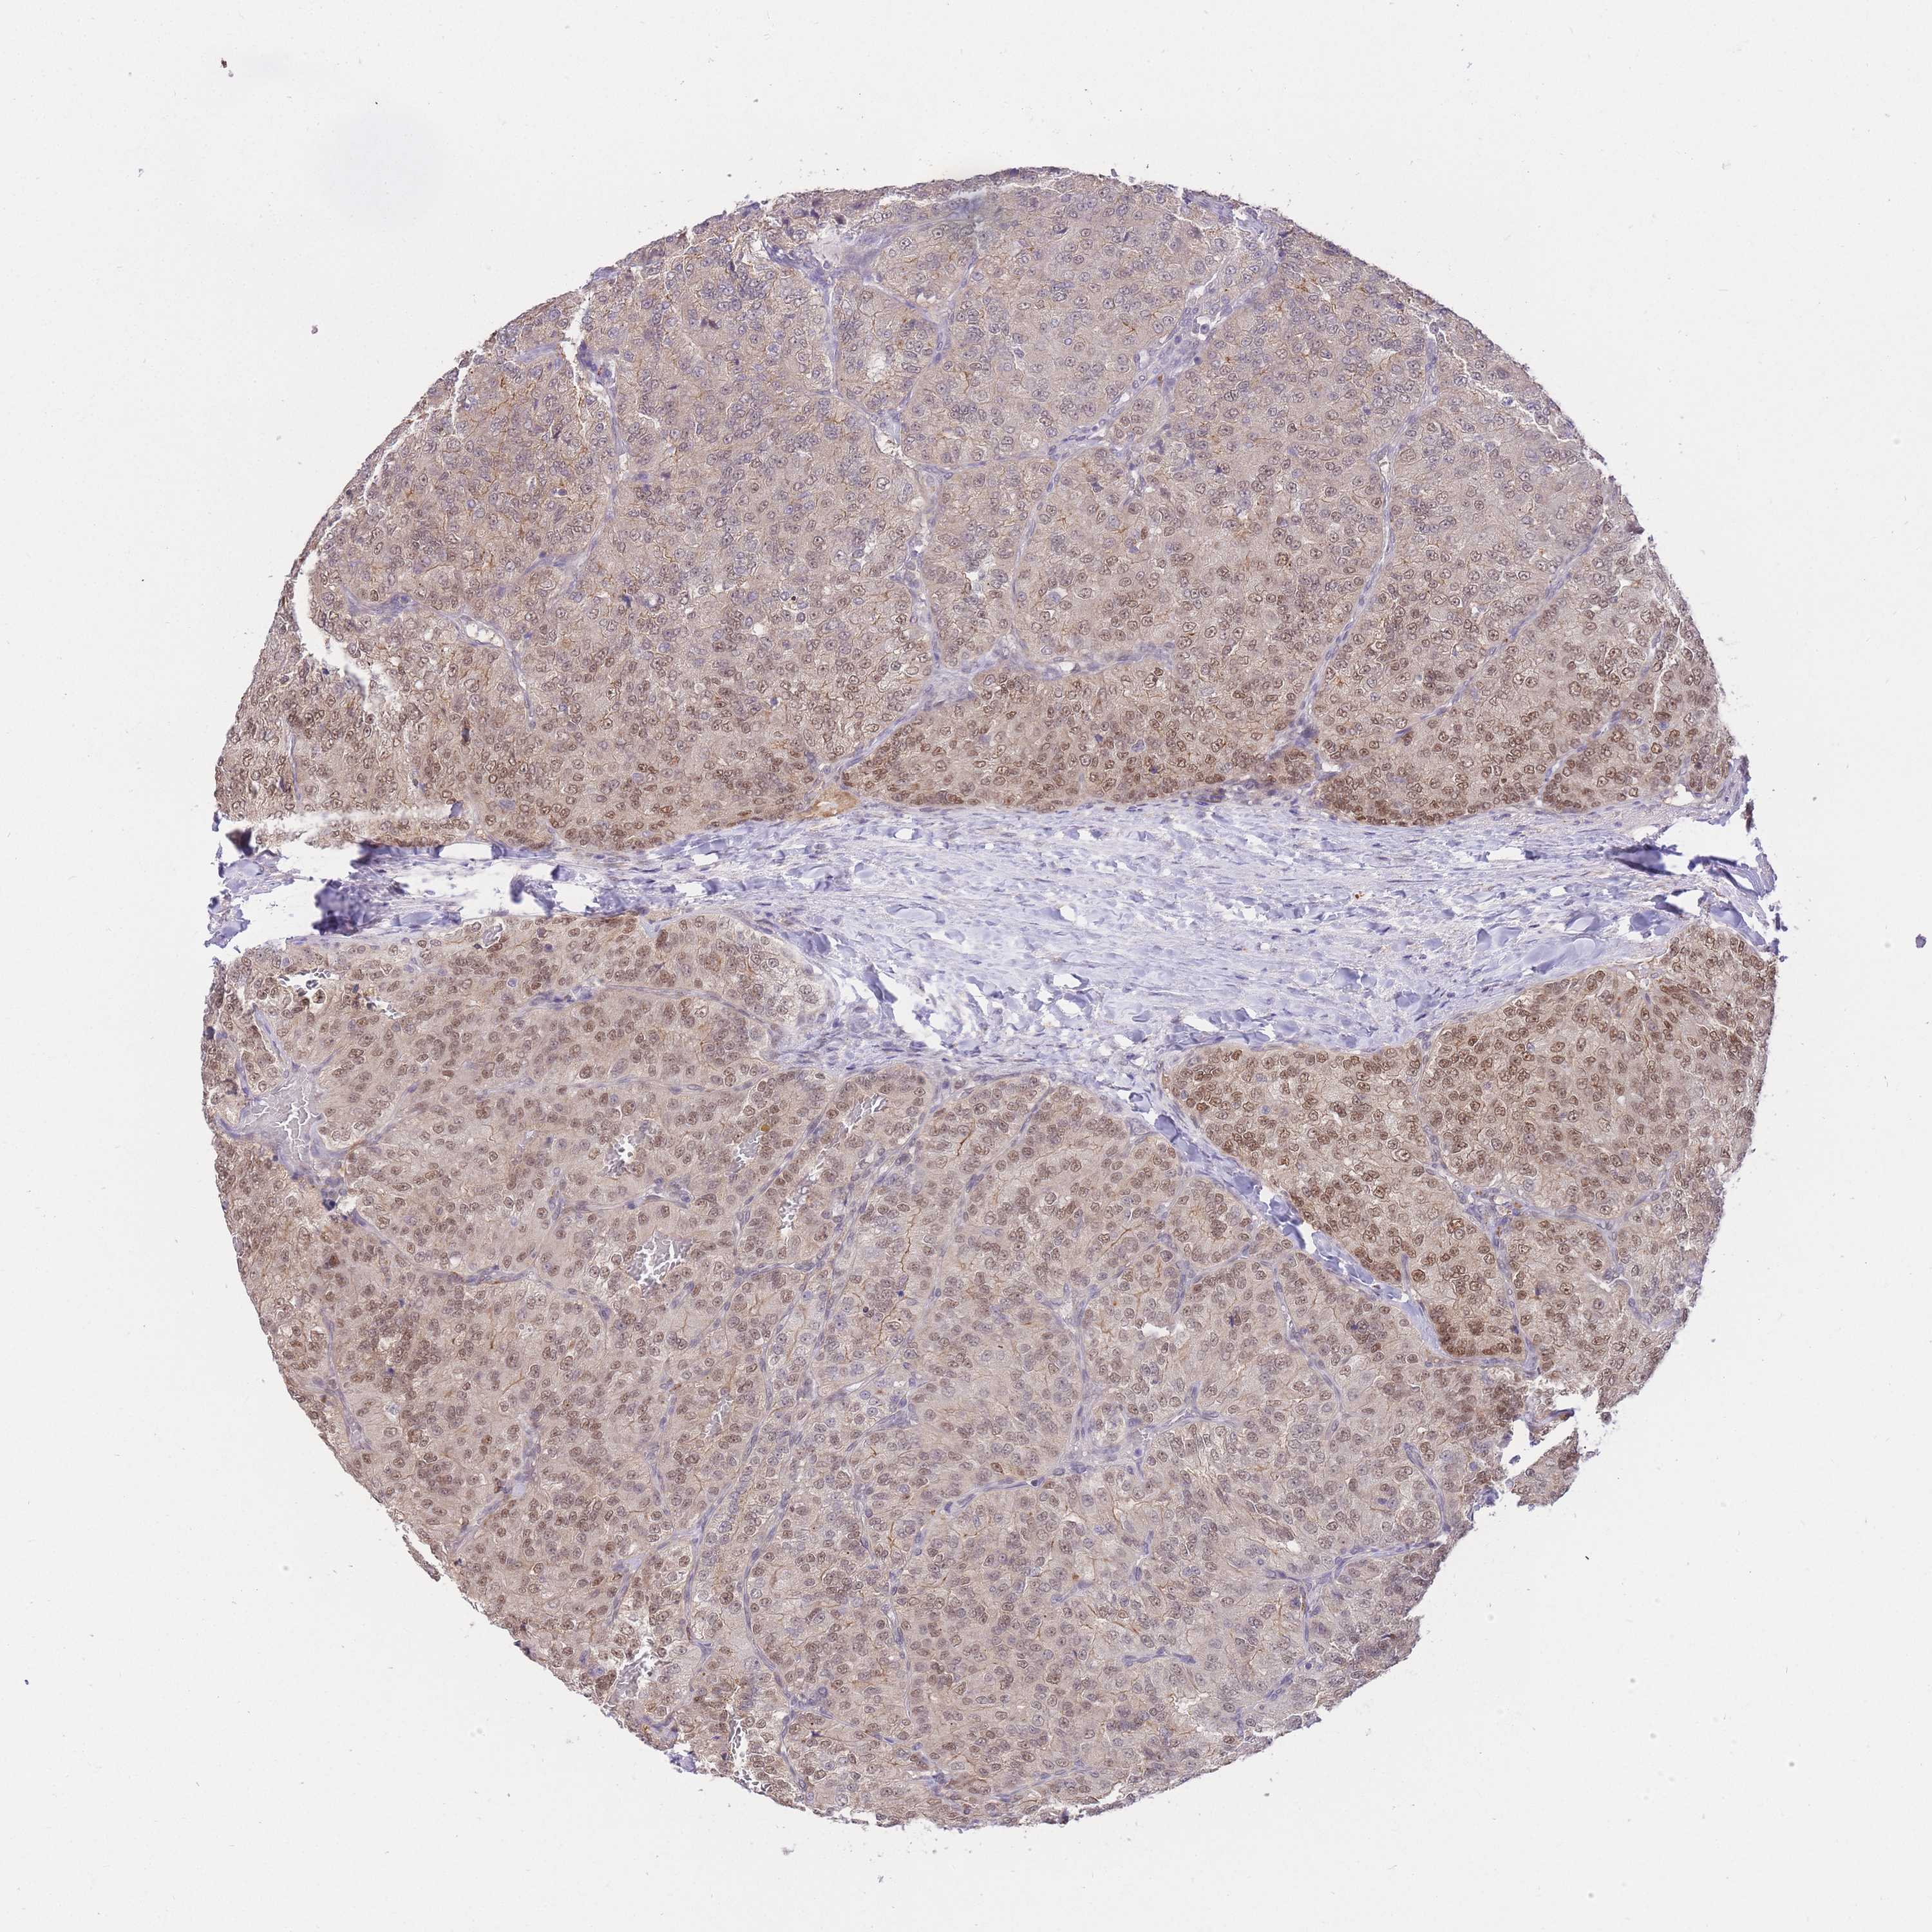

KIDNEY RENAL CLEAR CELL CARCINOMA (TCGA) - Interactive survival scatter ploti

The Survival Scatter plot shows the clinical status (i.e. dead or alive) for all individuals in the patient cohort, based on the same data that underlies the corresponding Kaplan-Meier plots. Patients that are alive at last time for follow-up are shown in blue and patients who have died during the study are shown in red.

& Survival analysisi

Kaplan-Meier plots summarize results from analysis of correlation between mRNA expression level and patient survival. Patients were divided based on level of expression into one of the two groups "low" (under cut off) or "high" (over cut off). X-axis shows time for survival (years) and y-axis shows the probability of survival, where 1.0 corresponds to 100 percent.

UBXN7 is not prognostic in Kidney Renal Clear Cell Carcinoma (TCGA)

Best expression cut offi

Based on the FPKM value of each gene, patients were classified into two groups and association between prognosis (survival) and gene expression (FPKM) was examined. The best expression cut-off refers the FPKM value that yields maximal difference with regard to survival between the two groups at the lowest log-rank P-value. Best expression cut-off was selected based on survival analysis .

: 6.54

Median expressioni

: N/A

P scorei

N/A

TCGA RNA samplesi

Average pTPM 6.9

Number of samples 521